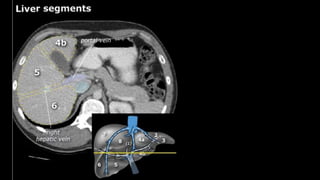

•Liver • A normalliver enhances homogeneously (irrespective of the scan phase). The liver receives about 80% of its blood through the portal vein (= nutrient-rich blood from the intestines). The remaining 20% is supplied by the hepatic artery. y is present, it is important to document its location. This may be crucial to any surgical options. Using the Couinaud classification, the liver is subdivided into eight individually functioning segments. Each segment has its own afferent hepatic artery and portal vein, and efferent hepatic vein and efferent bile ducts

y is present, it is important to document its

location. This may be crucial to any surgical options. Using the

Couinaud classification, the liver is subdivided into eight individually

functioning segments. Each segment has its own afferent hepatic

artery and portal vein, and efferent hepatic vein and efferent bile

ducts